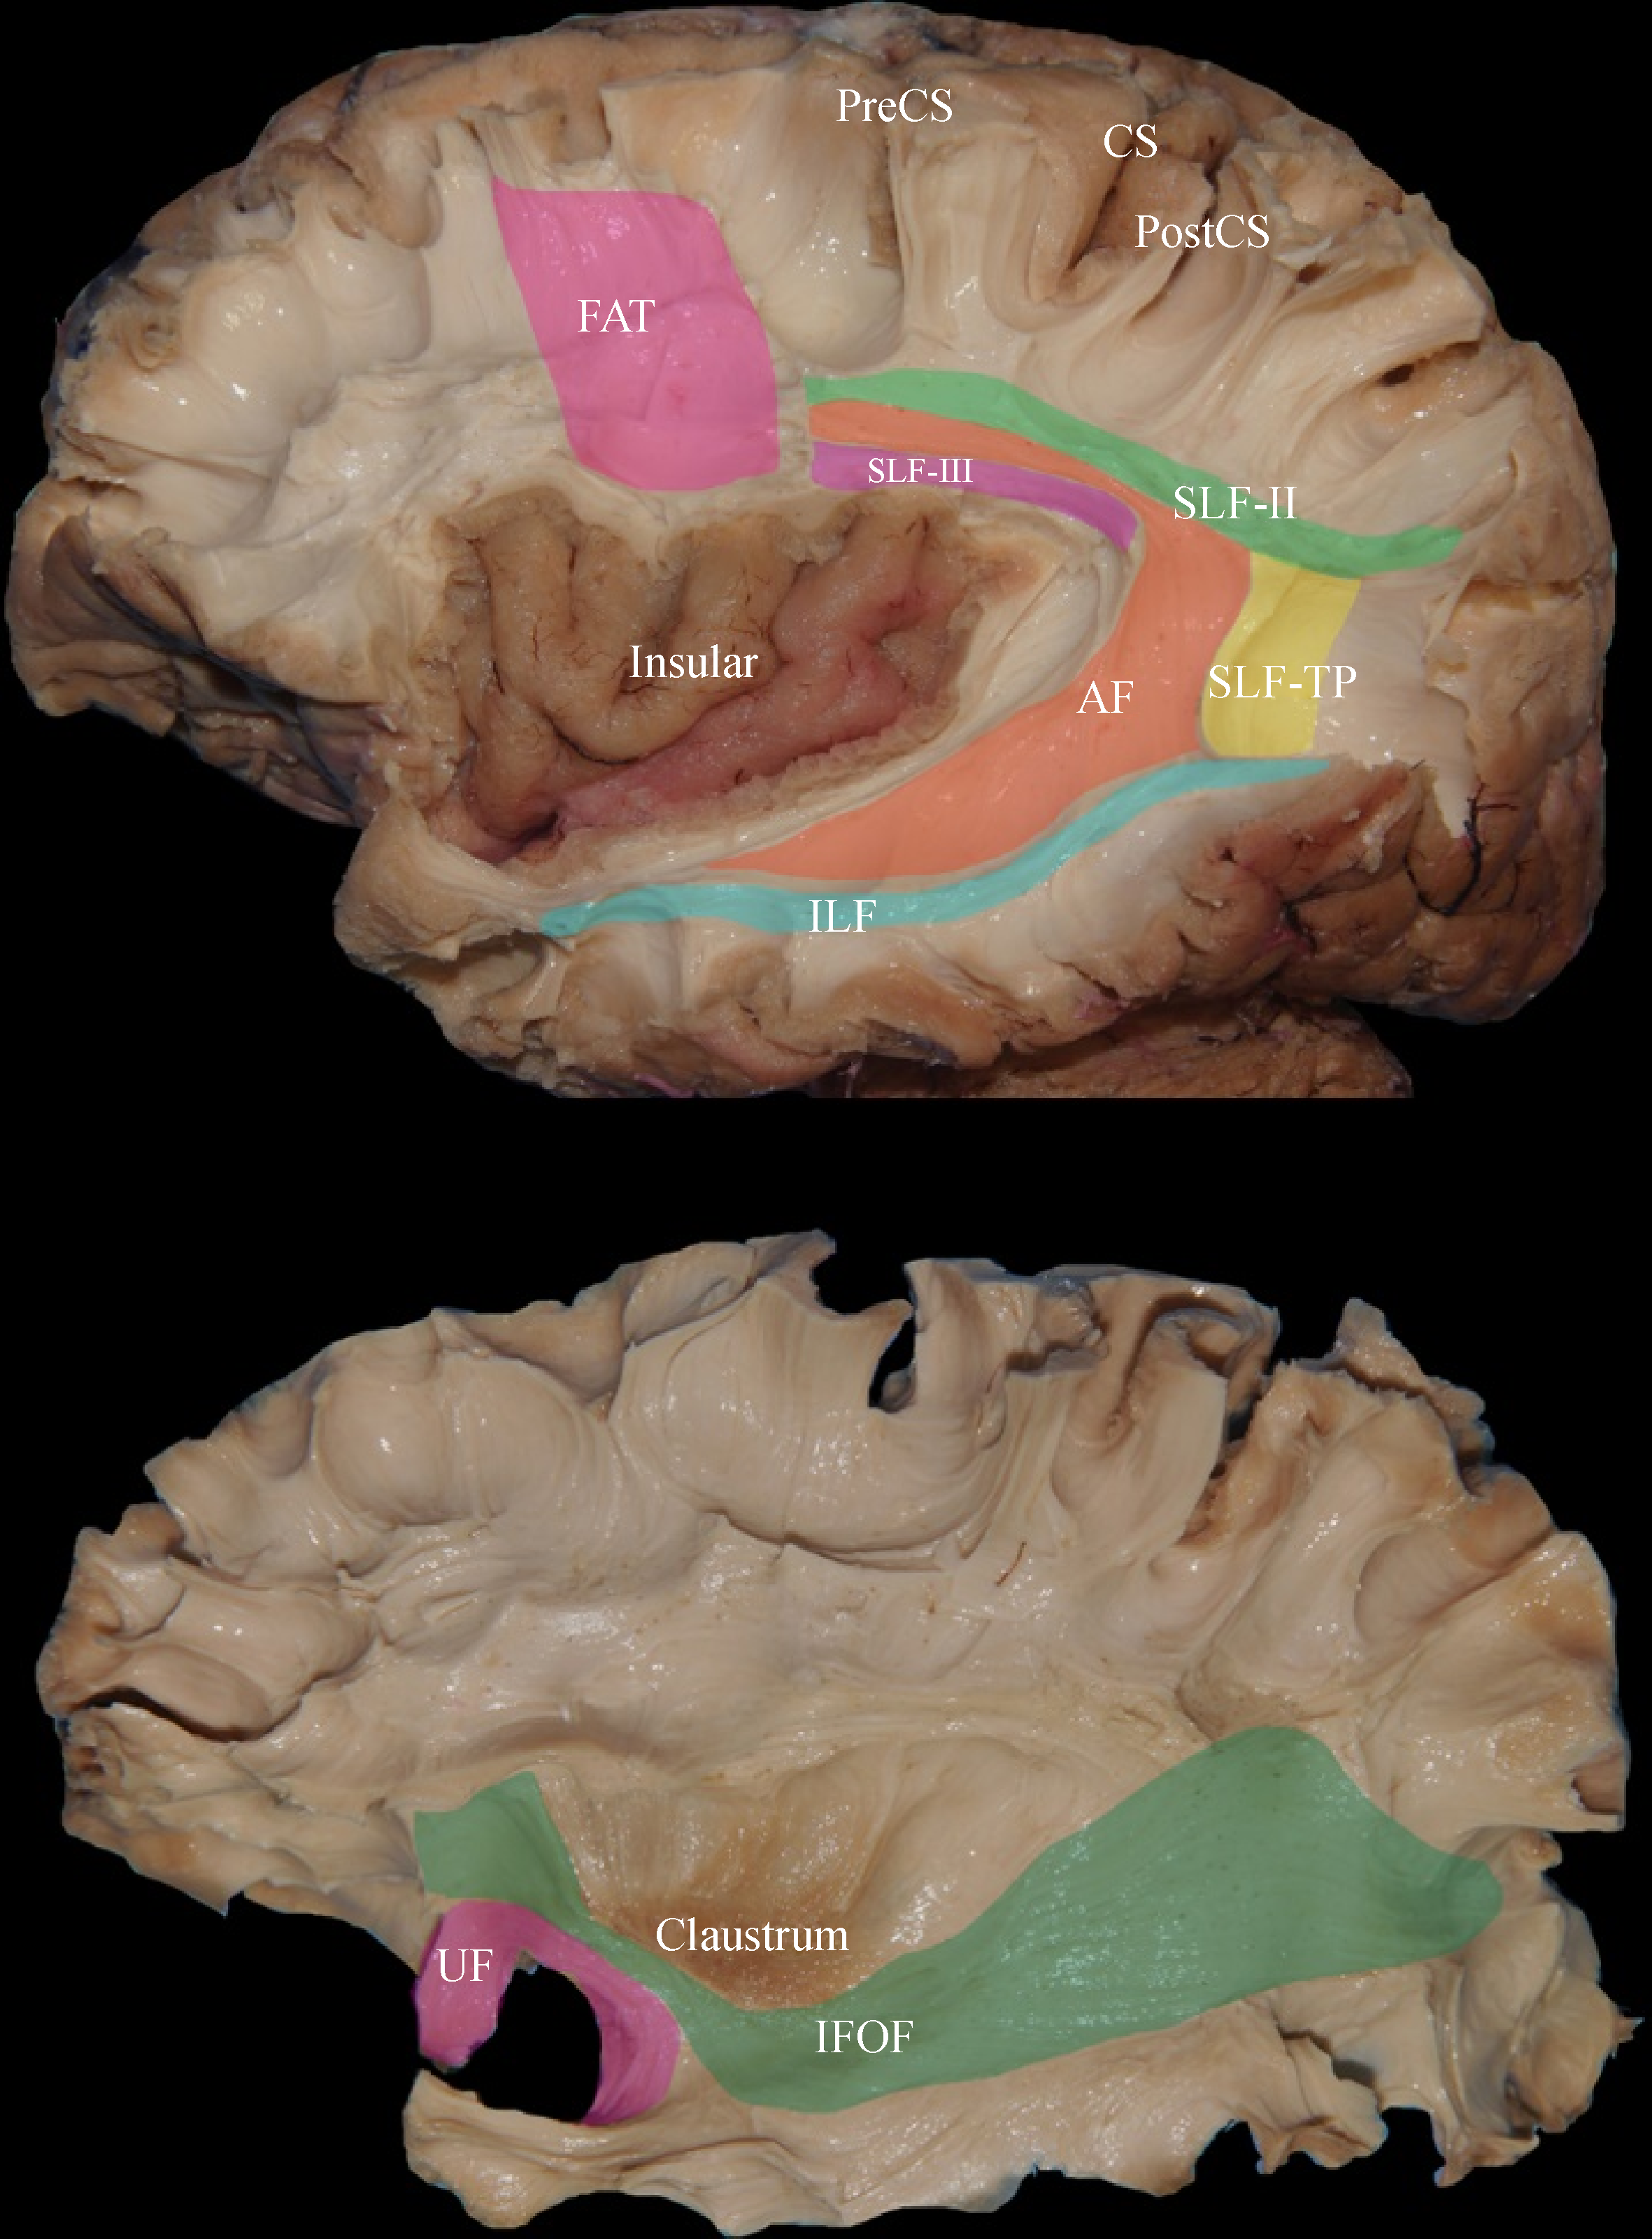

Peng Wang, Zehao Zhao, Linghao Bu, Nijiati Kudulaiti, Qiao Shan, Yuyao Zhou, N. U. Farrukh Hameed, Yangming Zhu, Lei Jin, Jie Zhang, Junfeng Lu, Jinsong Wu

The protection of language function is one of the major challenges of brain surgery. Over the past century, neurosurgeons have attempted to seek the optimal strategy for the preoperative and intraoperative identification of language-related brain regions. Neurosurgeons have investigated the neural mechanism of language, developed neurolinguistics theory, and provided unique evidence to further understand the neural basis of language functions by using intraoperative cortical and subcortical electrical stimulation. With the emergence of modern neuroscience techniques and dramatic advances in language models over the last 25 years, novel language mapping methods have been applied in the neurosurgical practice to help neurosurgeons protect the brain and reduce morbidity. The rapid advancements in brain--computer interface have provided the perfect platform for the combination of neurosurgery and neurolinguistics. In this review, the history of neurolinguistics models, advancements in modern technology, role of neurosurgery in language mapping, and modern language mapping methods (including noninvasive neuroimaging techniques and invasive cortical electroencephalogram) are presented.